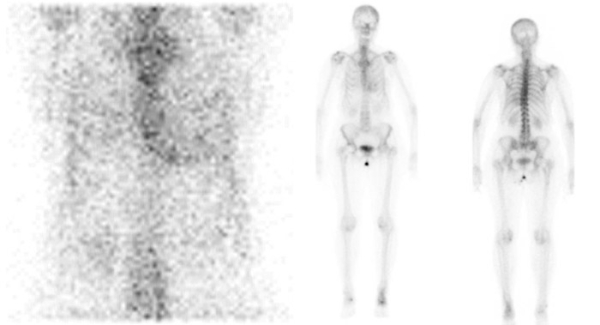

Ayant éliminé une amylose AL, l’examen complémentaire à réaliser permettant de rechercher une amylose cardiaque à transthyrétine (TTR) a été en priorité la scintigraphie corps entier au DPD ou au HMDP.

Figure 2 : scintigraphie corps entiers au DPD aux temps tardifs objectivant une hyperfixation cardiaque sans extinction de la trame osseuse (stade 2 de Perugini)

Figure 3 : coupes tomographiques cardiaques couplées à la scintigraphie corps entiers au DPD, confirmant l’hyperfixation du myocarde (et non pas du pool sanguin intracardiaque comme parfois observé en cas de ralentissement du flux sanguin).

Comme vous le voyez, les images de la scintigraphie, réalisées aux temps tardifs, mettent en évidence chez la patiente une hyperfixation de l’aire cardiaque sur les vues corps entier (Figure 2). L’évaluation est semi-quantitative et classée par le médecin nucléariste stade 2 de Perugini. Cette hyperfixation myocardique très caractéristique est ensuite confirmée sur les coupes tomographiques (Figure 3). Ceci est primordial car l’une des causes possibles de faux positif est la fixation du pool sanguin intracardiaque en cas de ralentissement du flux sanguin.

Comme souvent dans les atteintes précoces d’amyloses cardiaques à TTR, les anomalies prédominent ici au niveau de la paroi septale du VG et en latéral basal.